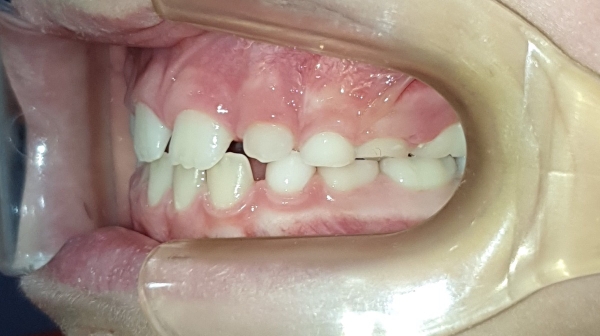

DESPUÉS